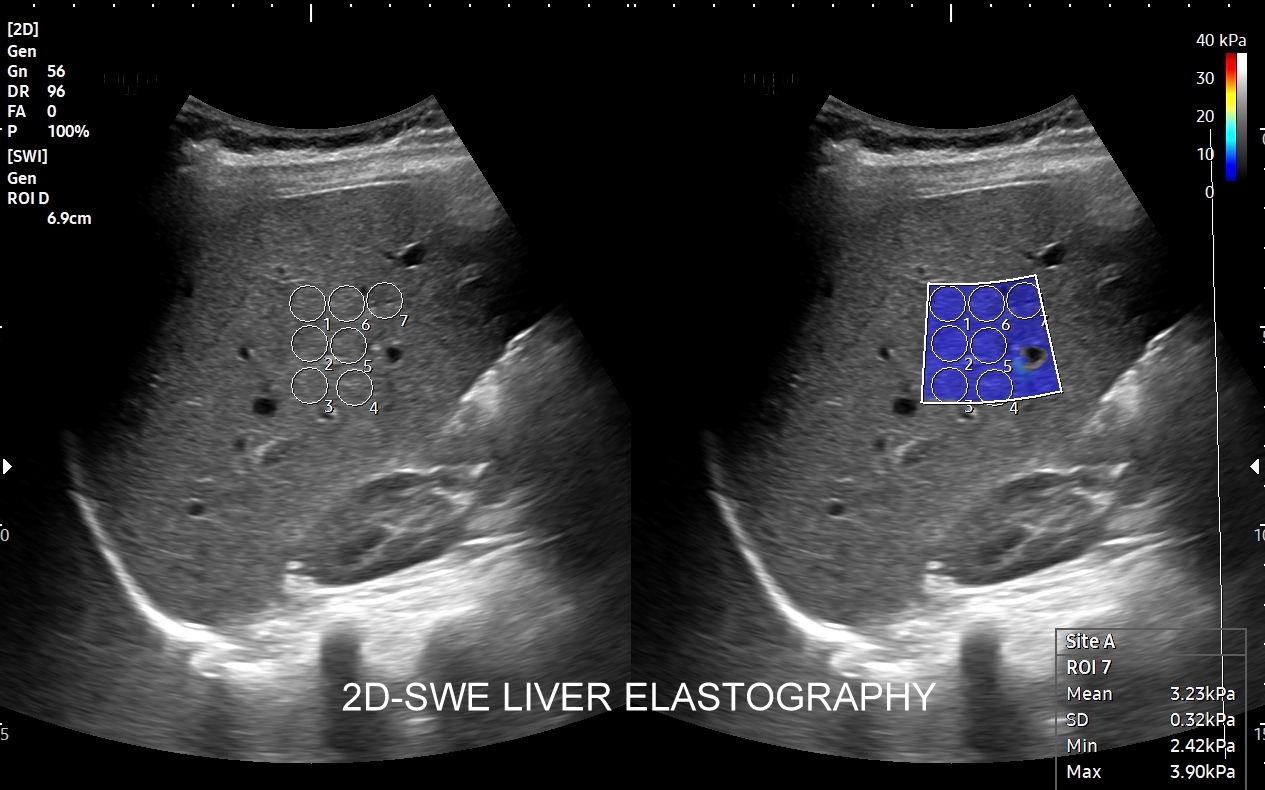

Na przestrzeni czasu metoda SWI ulegała ewolucji. Jej starsza odmiana to tzw. Fibroscan, który jest badaniem „na ślepo”, gdyż nie umożliwia precyzyjnego wyboru miejsca oceny miąższu wątroby. Odmianą najnowszą i wysoce precyzyjną jest elastografia 2D-SWE (2D sheer wave elastography). W badaniu 2D-SWE możliwy jest wybór konkretnego miejsca pomiaru w obrębie wątroby; dodatkowo generowana jest mapa kodowaną kolorem odpowiadająca mnogim punktom pomiaru, które następnie w trakcie post-processingu można wybrać w celu uzyskania dokładnego i wiarygodnego wyniku.

W jakim celu wykonywana jest elastografia wątroby? Elastografia 2D-SWE precyzyjnie ocenia sztywność miąższu wątroby, która to wzrasta w procesie włóknienia na tle przewlekłych schorzeń narządu, np. zapaleń. Badanie pozwala w ten sposób ocenić stopień zaawansowania zwłóknienia lub marskości wątroby. Dokładność oszacowania zwłóknienia w elastografii 2D-swe jest na tyle precyzyjna, iż zastępuje ona w omawianym wskazaniu medycznym biopsję wątroby.